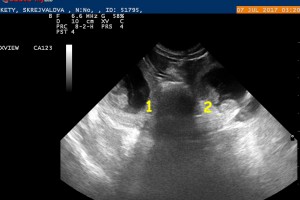

7.7. Čekáme 6 štěňátek

Přesně 30. den gravidity jsem zopakovala sono a Kety má v bříšku 6 malých štěkátek. Bytečky pro štěňátka jsou skoro 3 cm velké a v nich plavou už skoro 1cm velcí červíčci, u kterých už jsou rozeznatelné jednotlivé části těla a bijící srdíčka. Tak hlavně, aby to nadále bylo bez problémů.